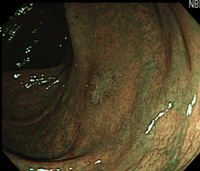

A:NBIで発見された陥凹型腫瘍。

-

B:同部位の通常観察像。通常観察では発見困難である。